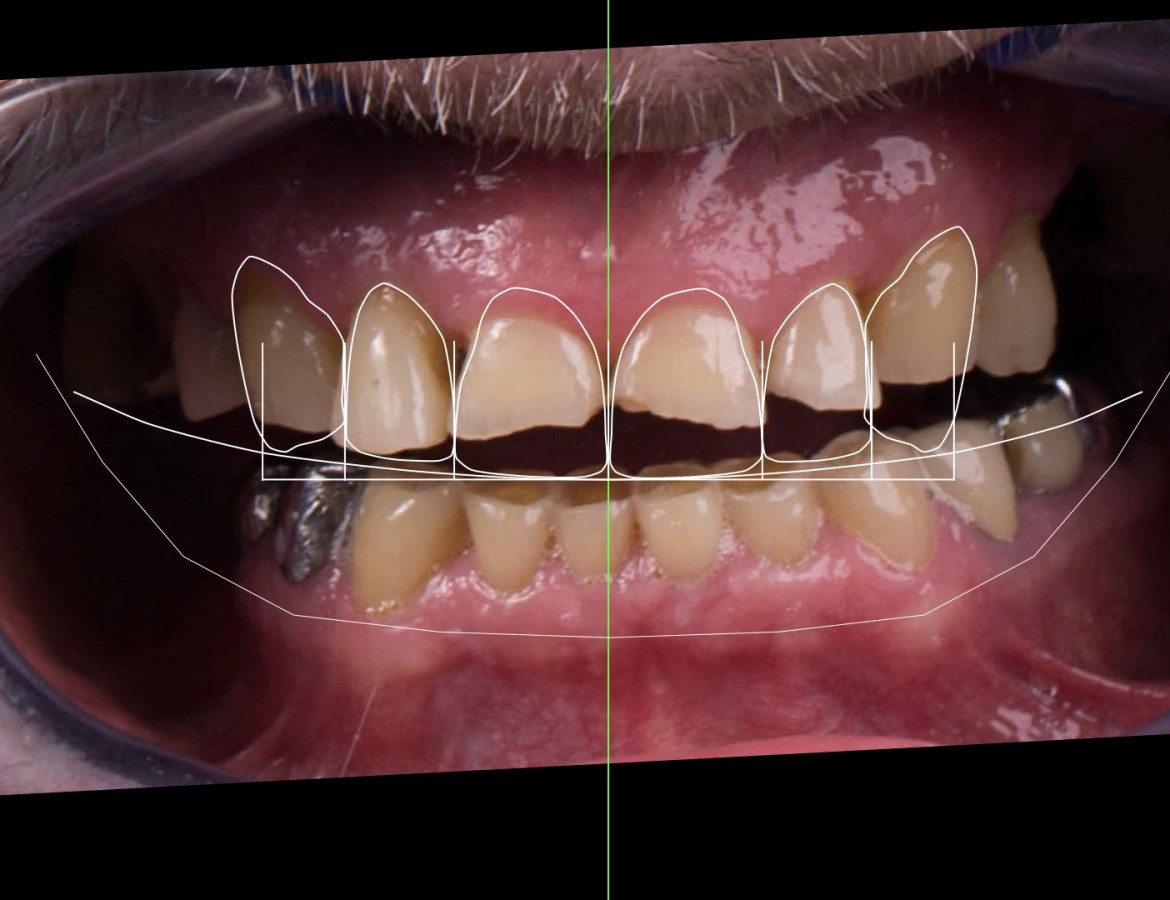

Pan Ludovít se rozhodl pro razantní změnu úsměvu. Trápila ho bolest zubů postižených paradentózou a esteticky nevyhovující přední zuby. Po vstupním vyšetření a iniciální fázi u dentální hygienistky jsme navrhli panu Ludovítovi ortodontickou léčbu pro zlepšení postavení předních a zadních zubů. Po ortodontické léčbě jsme provedli důkladné paradentologické vyšetření a provedli ohlazení paradentózou postižených zubů. Po zavedení 4 implantátů jsme zhotovili dlouhodobá provizoria pro stabilizaci skusu. Následně jsme zuby miniinvazivně napreparovali na keramické korunky. Porovnejte stav před a po léčbě. Pan Ludivít je štastný a my s ním, protože štěstí začíná úsměvem.